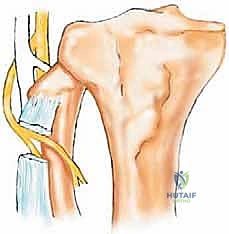

The successful execution of a Type I resection demands a profound, three-dimensional understanding of the regional anatomy, particularly the relationship between the proximal fibula, the lateral ligamentous complex of the knee, and the common peroneal nerve. The overarching goal of this procedure is strictly twofold: to achieve wide oncologic margins to prevent local recurrence, and to reconstruct the lateral stabilizing structures of the knee to prevent devastating postoperative varus and posterolateral rotatory instability.

The proximal fibula, comprising the fibular head, neck, and proximal metaphysis, acts as an essential stabilizing pivot point for the posterolateral corner (PLC) of the knee. It serves as the primary attachment site for the fibular collateral ligament (FCL/LCL), the biceps femoris tendon, the popliteofibular ligament, and the arcuate ligament. The conjoined insertion of the LCL and biceps femoris onto the fibular styloid process dictates lateral knee joint stability, resisting varus stress, external tibial rotation, and posterior tibial translation.

The most critical anatomical structure in this region is the common peroneal nerve (CPN). As the nerve descends from the popliteal fossa, it courses obliquely along the medial border of the biceps femoris tendon. It then wraps superficially around the fibular neck, passing deep to the tendinous origin of the peroneus longus muscle to enter the peroneal tunnel. Within this fibro-osseous tunnel, the nerve bifurcates into the superficial and deep peroneal nerves, which supply the lateral (eversion) and anterior (dorsiflexion) compartments of the leg, respectively.

During a Type I resection, the CPN must be meticulously identified, neurolysed, and protected, unless oncologically compromised. The anterior tibial artery, a terminal branch of the popliteal artery, also passes in close proximity to the proximal fibula, traversing the hiatus in the interosseous membrane from the posterior to the anterior compartment. Ligation of the anterior tibial recurrent artery is universally necessary to mobilize the neurovascular bundle safely without tethering.

The first and most critical deep step is the identification of the common peroneal nerve. The nerve is located proximal to the tumor, medial to the biceps femoris tendon in the popliteal fossa. Once identified, vessel loops are utilized to provide gentle traction. The nerve is traced distally as it winds around the fibular neck. The fascia over the peroneal compartment is incised, and the peroneus longus muscle is retracted or divided to unroof the peroneal tunnel. The superficial and deep branches of the peroneal nerve are systematically neurolysed and mobilized away from the tumor pseudocapsule. If the tumor directly abuts or encases the nerve, the nerve must be sacrificed to achieve a wide oncologic margin.